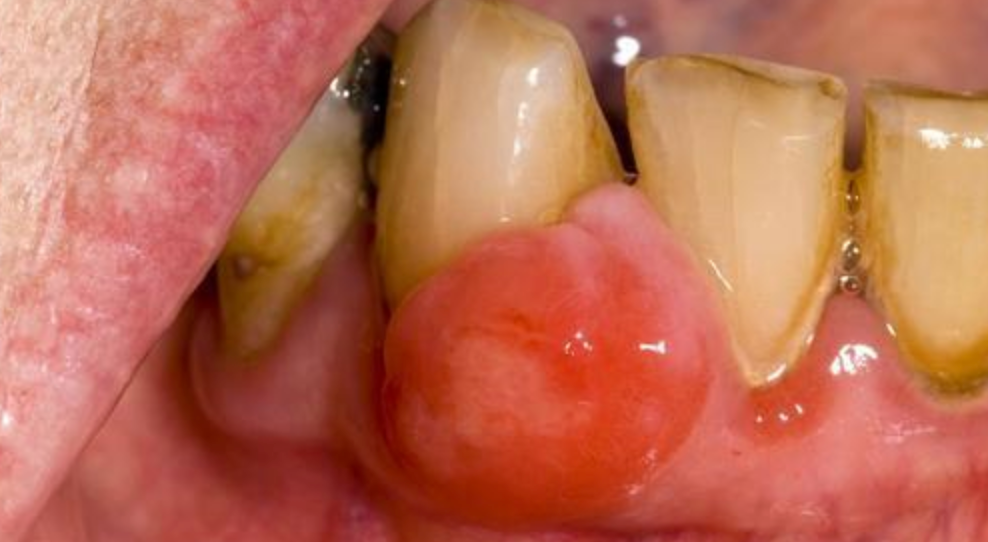

牙龈红肿出血,刷牙时满嘴血腥味?这是牙龈炎的典型信号。单纯问“吃什么药”往往治标不治本,急性期可短期用药控制炎症,但彻底缓解需配合专业洁牙与日常护理。